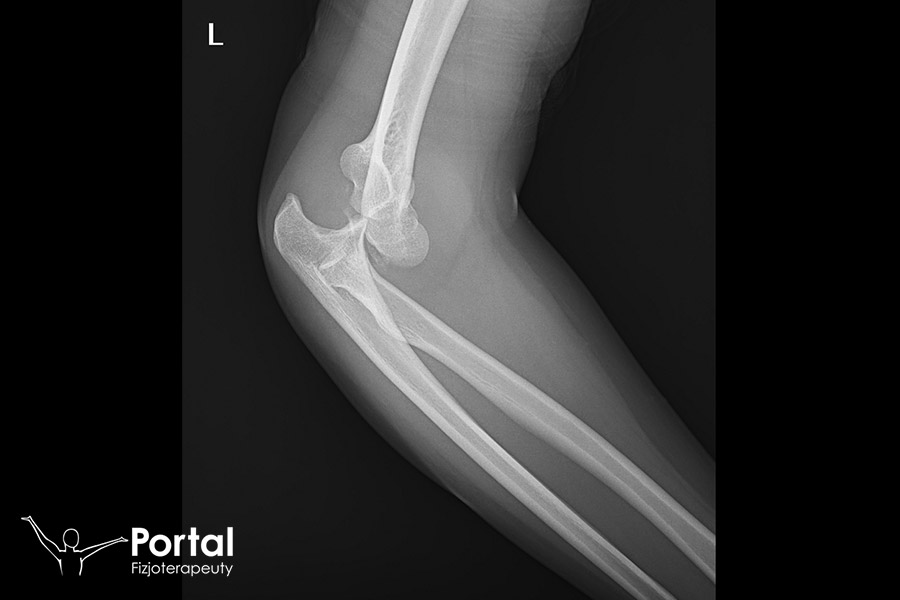

Wszystko to określa się jako inkongruencja, czyli przeciwnie do kongruencji – niezgodność, niestosowność. W ujęciu medycznym inkongruencja najczęściej dotyczy właśnie niedopasowania powierzchni stawowych. Na końcu należy zaznaczyć, że zachowanie właściwej kongruencji ma ogromne znaczenie na oddziałach ortopedycznych, gdzie wykonuje się nastawianie kości i stawów po urazach (np. zwichnięciach). Błędne nastawienie stawu, związane z niedopasowaniem powierzchni stawowych, będzie wymagać np. operacji lub ponownego nastawienia, ponieważ uniemożliwi sprawne i bezbolesne wykonywanie ruchów w tym stawie.